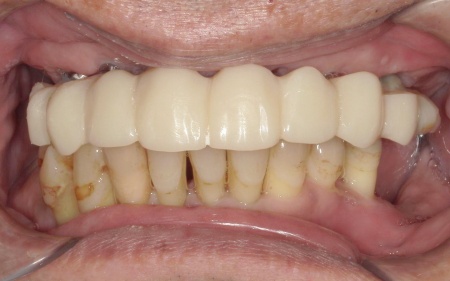

50代男性 抜歯と同時にインプラントを埋めて歯を補った症例

①上の歯7本、右下の奥歯2本を抜歯する。上あごには抜歯と同時に4本のインプラントを埋め、その上に10本分の仮歯を取り付けるオールオンフォーを行う。

②インプラントが安定したことを確認してから、仮歯を外して最終的な人工歯を装着する

最後に、残っている下の歯としっかりと噛み合っていることを確認し、治療を終了しました。